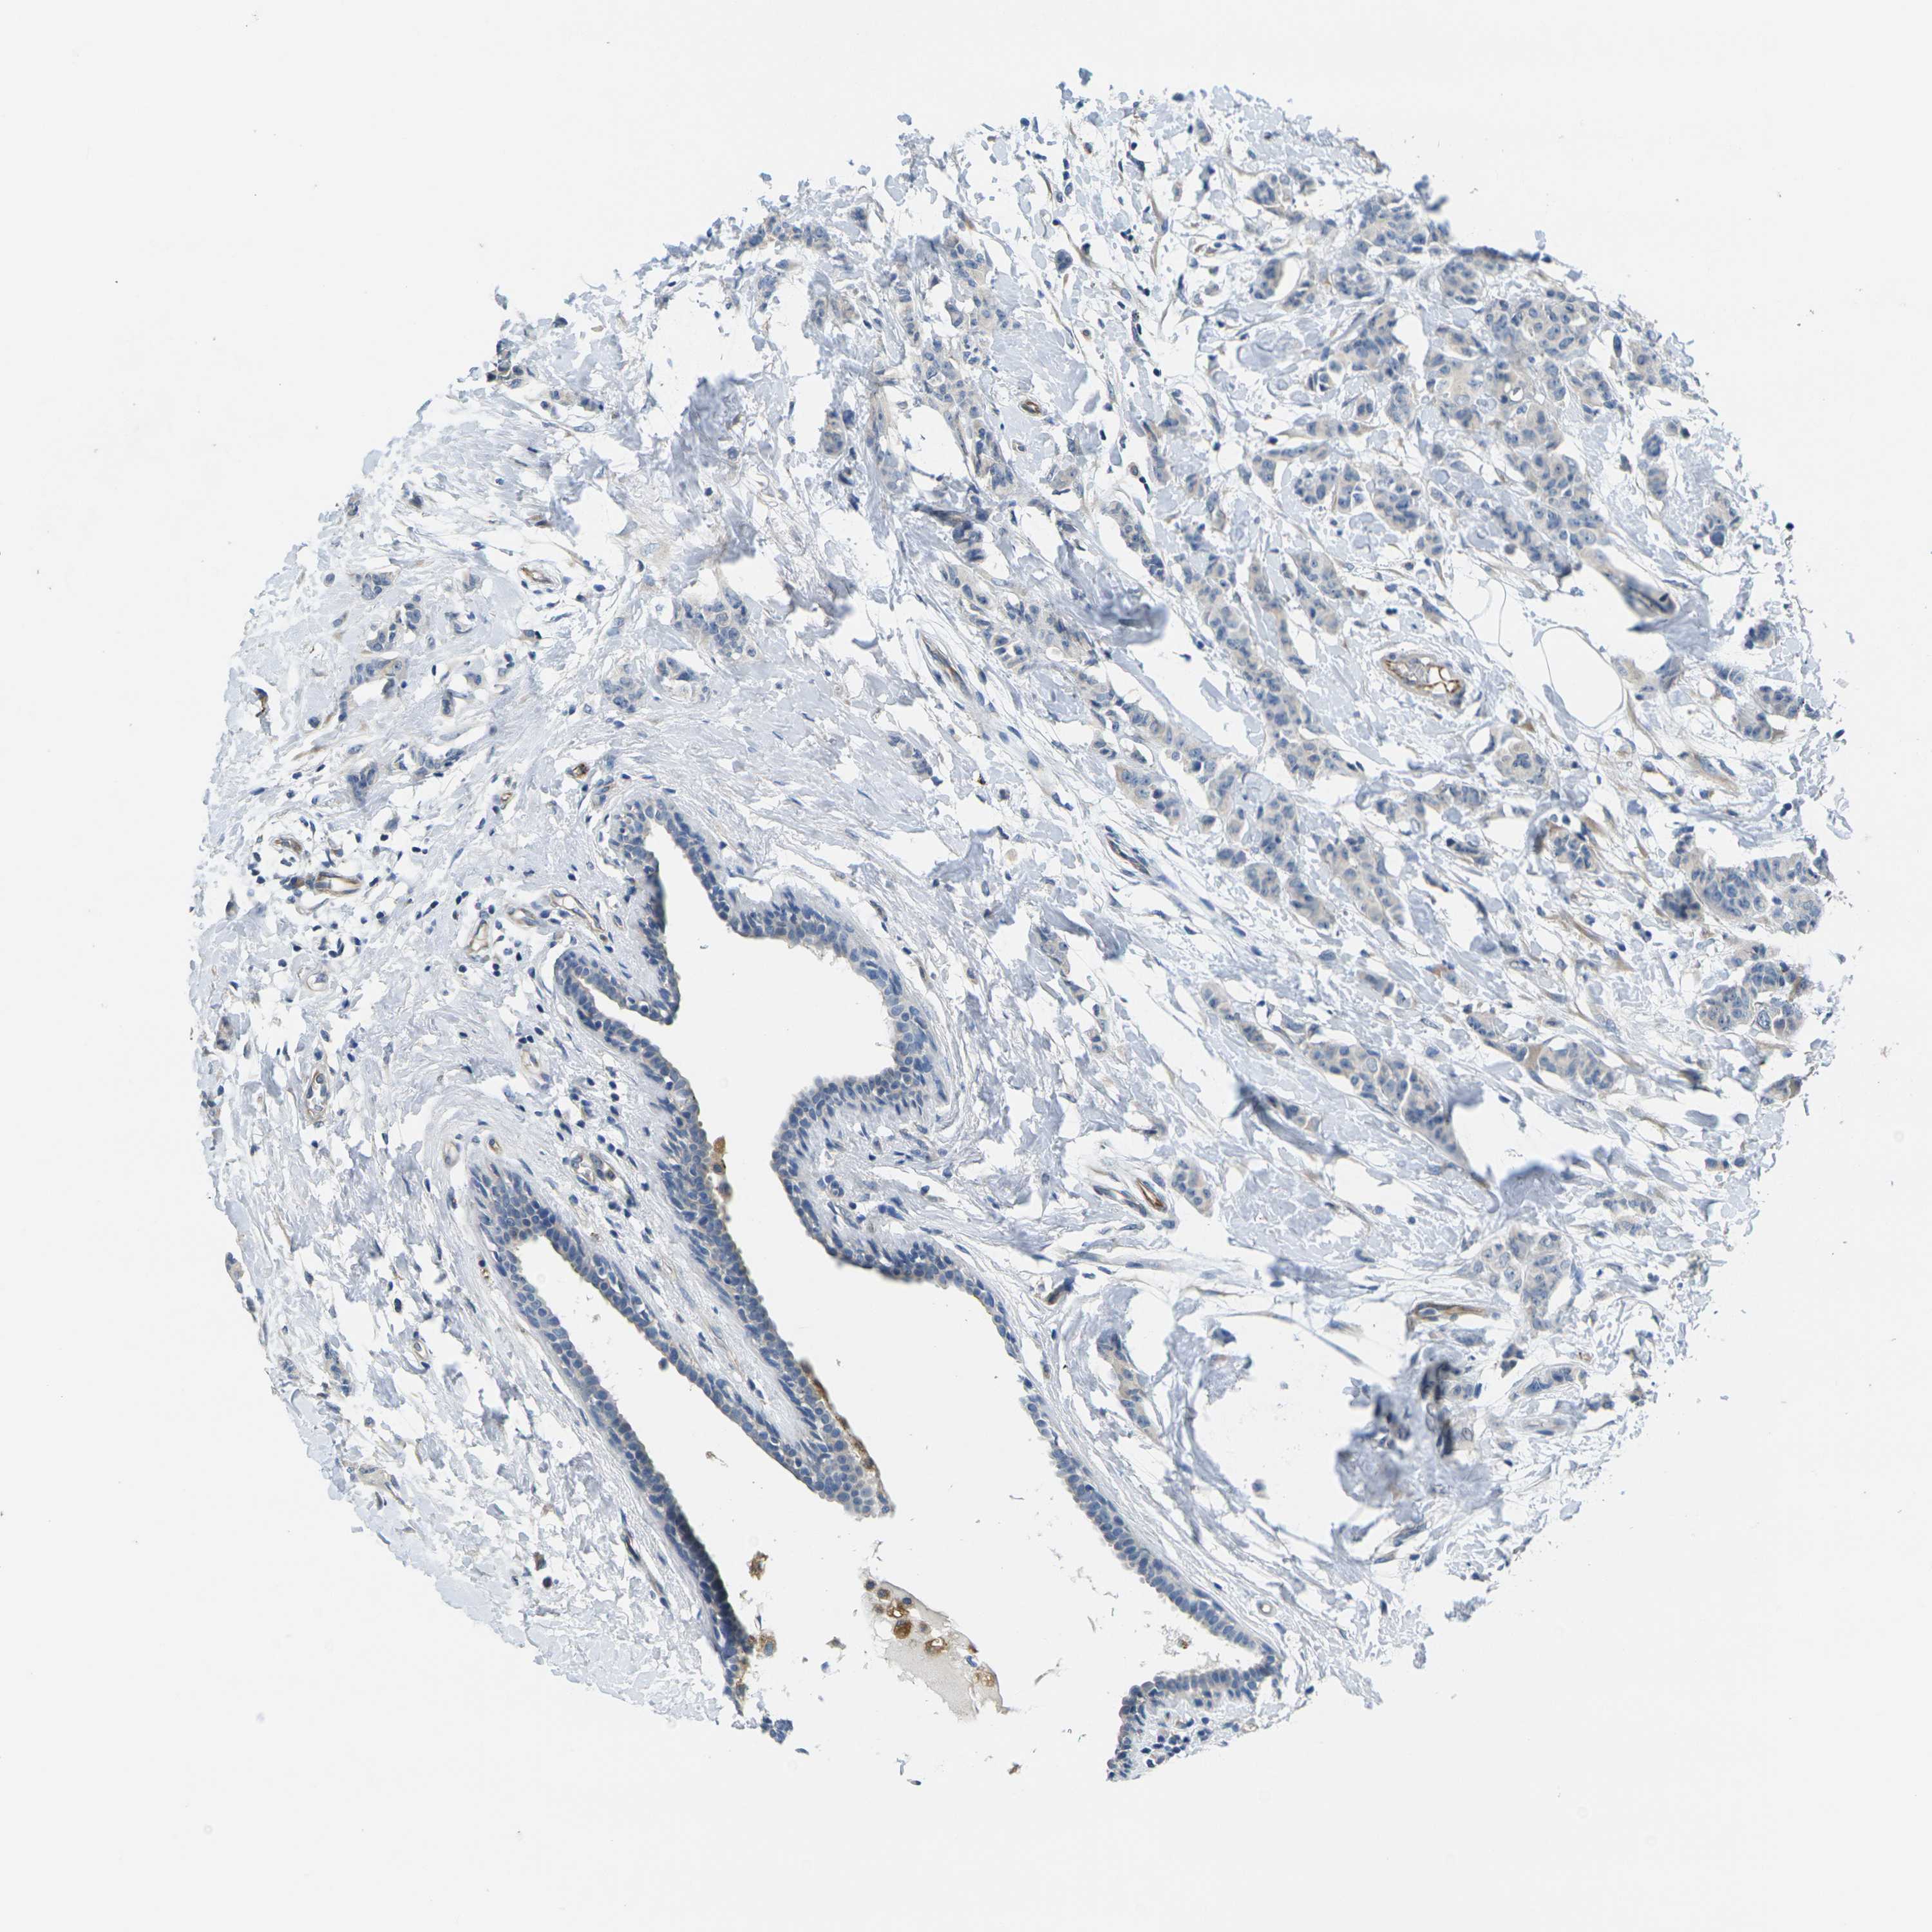

CANCER BREAST CANCER Show tissue menu

BRCA TCGA BRCA VALIDATION PROTEIN EXPRESSION

ANTIBODIES

AND

VALIDATION